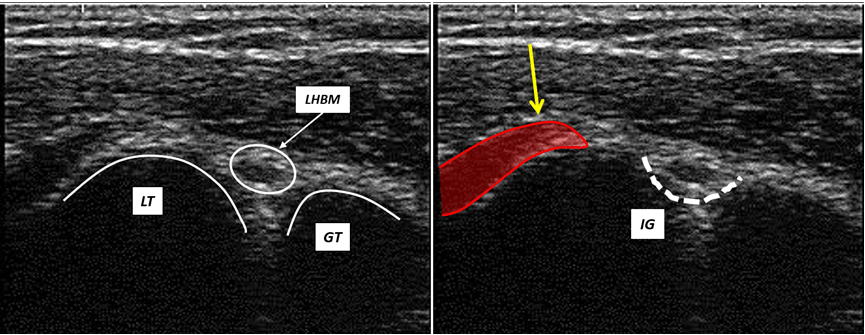

The ultrasound transversal view can be classified into four types (Figures 1,2,3,4).

Figure 1: Ultrasound transversal view Type I: The fibers (yellow arrow) of the SCM tendon are exclusively attached to the lesser tubercle; LT = lesser tubercle; GT = greater tubercle; IG = intertubercular groove; LHSM = long head of biceps muscle.